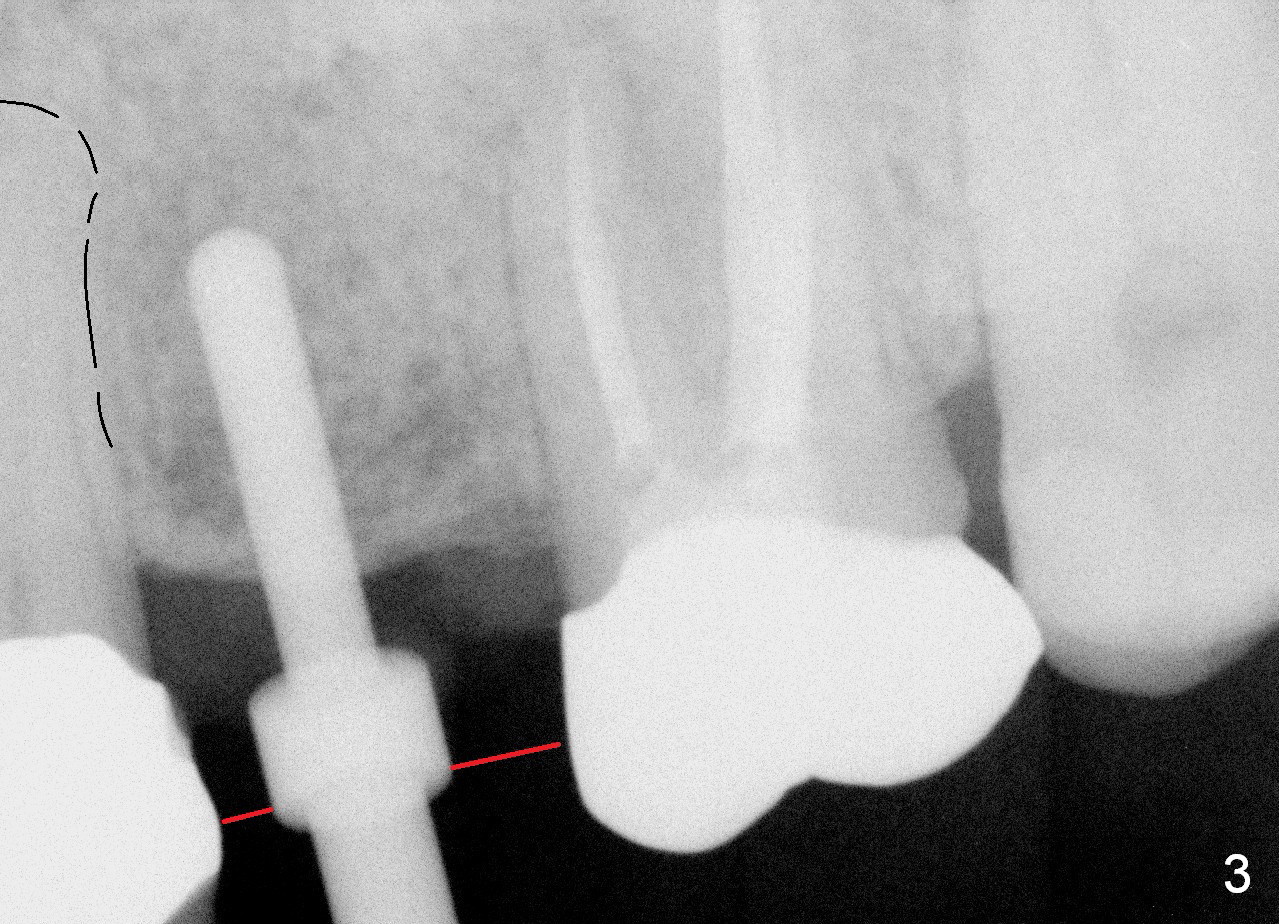

A 45-year-old lady is nervous about dental treatment. The missing tooth #13 was replaced by a 3-unit bridge. The latter is sectioned because the posterior abutment has caries. PA in Fig.1 is taken when root canal therapy and build up are finished. Fig.2 shows the wide edentulous area with a single-unit crown being tried in for #14. Osteotomy is initiated with the crown in place without cementation, since it is easy to determine the mesiodistal position (Fig.3 red lines). Without the crown in place, osteotomy tends to be distal. In this case, the osteotomy is later attempted to be moved distally with Lindamann bur and deepened to 14 mm from the gingival margin (Fig.4). A 2.5 mm reamer is being used at 50 RPM to increase osteotomy with difficulty. Drills have to used at high RPM instead (Fig.5 4x14 mm). A 4.5x14 mm tissue-level implant is placed with insertion torque >60 Ncm (Fig.6 I); a 4x3 mm abutment (A) is placed immediately for an immediate provisional. Fig.7 is taken 7 days postop to show the gingival recipient site formed by the provisional. The patient is so afraid of X-ray that the next one is taken 1.5 years post cementation (Fig.8). It appears that dense bone bundle forms between the crest and the 1st implant thread (adaptation functional change, arrowheads). The bone density continues to increase 2 years 8 months post cementation (Fig.9 *, 10); the bone has grown into the area between the 1st 2 threads (arrow).